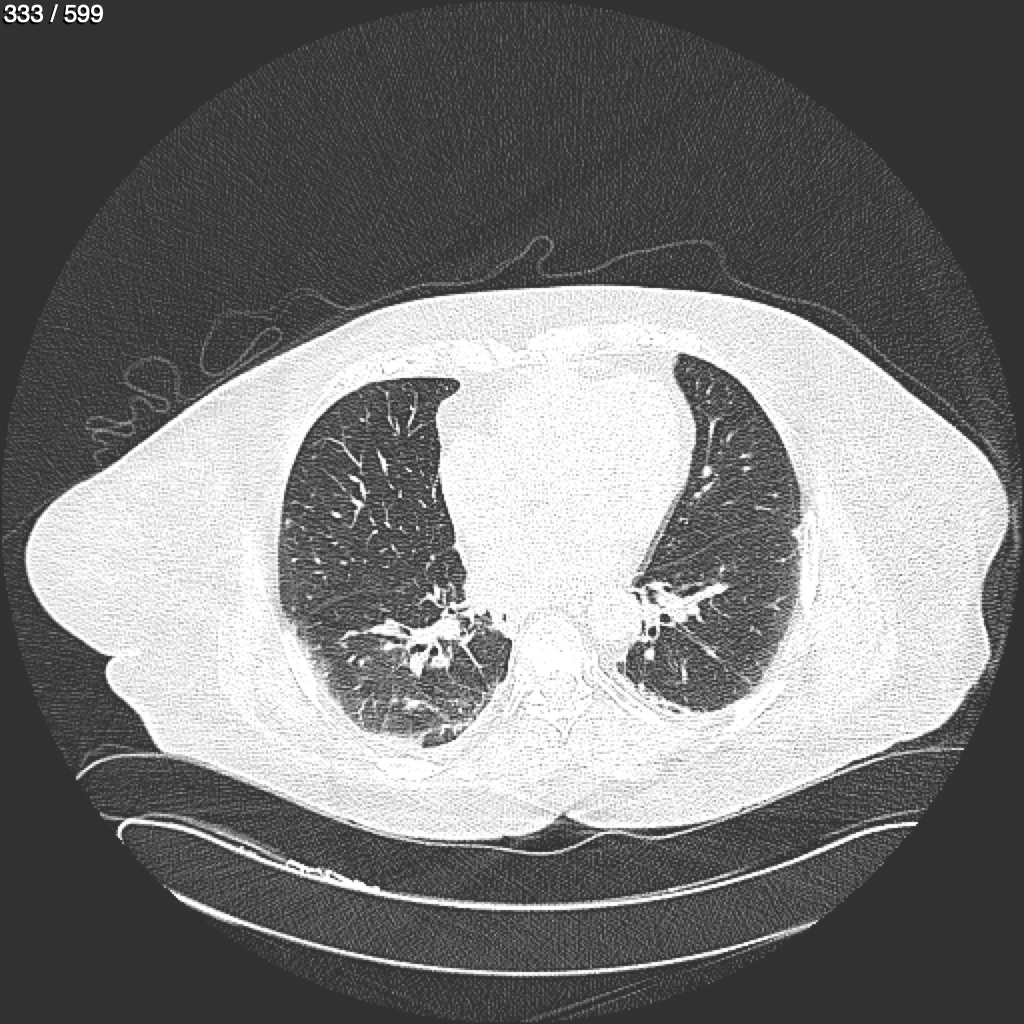

Home G​l​o​r​i​a​ ​G​l​a​d​y​s​ ​B​e​a​s​l​e​y​ ​-​ ​T​ó​r​a​x​ ​T​o​r​a​x​_​S​i​m​p​l​e​ ​(​A​d​u​l​t​o​)